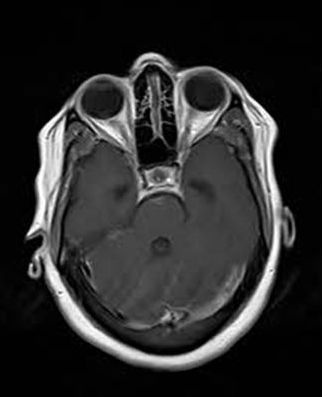

Background: Cavernous hemangiomas are common benign vascular malformations. Their existence in the intraventricular region is very rare. Case Reports: A 43-year old woman with an occipital headache was admitted to the emergency ward. Brain computed tomography scan showed mild hydrocephalus and multiple intraventricular isodense lesions. Imaging findings, especially of Gradient Resonance Echo imaging, were in favor of multiple intraventricular cavernous malformations. Conclusion: This is a rare presentation of multiple cavernous malformation as occipital headache without needing surgical intervention in this phase. Coexistence of periventricular plaques like Radiologically isolated syndrome of Multiple sclerosis is another unique aspect in this report. [GMJ.2017;6(1):61-65]